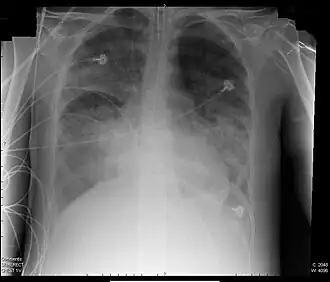

Röntgenfoto van een patiënt met ARDS | ||||

ARDS ontstaat op nog onbekende wijze ten gevolge van een ernstige ziekte van de longen zelf (bijvoorbeeld een longontsteking), of een ziekte elders in het lichaam. Door de ontstekingsreactie treden vocht, eiwitten en ontstekingscellen uit de longbloedvaten in het longweefsel. Hierdoor wordt de overdracht van zuurstof vanuit de longen naar het bloed bemoeilijkt, waardoor een tekort aan zuurstof in het bloed (hypoxemie) ontstaat. Op een röntgenfoto van de longen zijn in beide longen zogenoemde consolidaties te zien: opeenhopingen van vocht, cellen en afvalmateriaal.